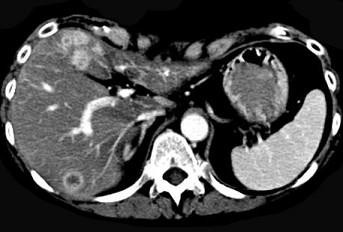

问题 继发性肝癌诊断的关键是 ( )

选项 A、行CT检查 B、测定血清甲胎蛋白 C、行肝动脉造影检查 D、行放射核素扫描 E、查清原发癌灶 单选题

答案 E